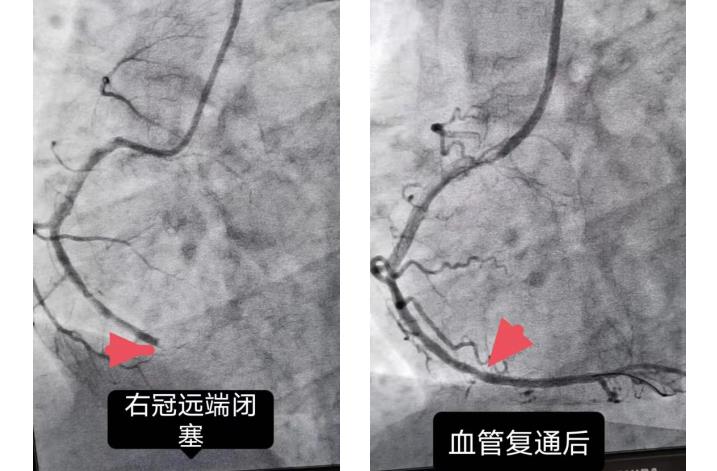

大众卫生报·新湖南客户端3月1日讯(通讯员 李三梅 袁雯 )2月26日晚,28岁的胡先生因持续胸痛6小时,就诊于湘潭市第一人民医院急诊科。经心电图提示窦性心律及Ⅱ、Ⅲ、AVF导联ST段上抬,快速肌钙蛋白阳性,急行冠脉造影显示右冠远端完全闭塞,确诊急性心肌梗死,开通绿色通道后立即送往导管室行血运重建,在植入药物支架一枚后,胸痛症状明显缓解。